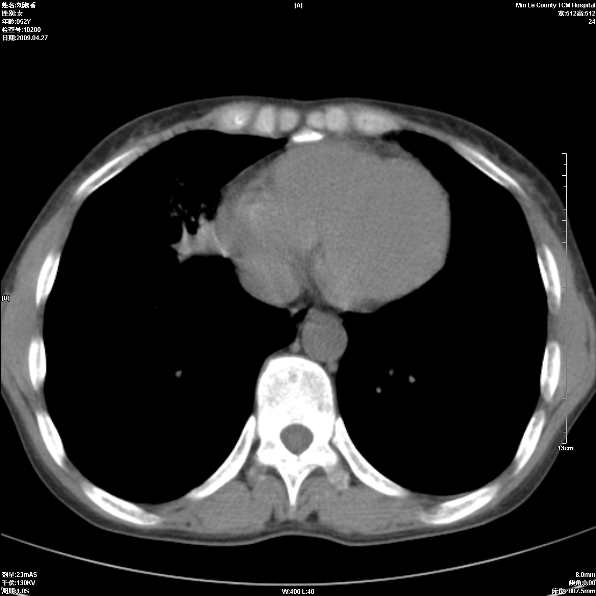

标题: CT19625:女52间断性喀血 [打印本页]

标题: CT19625:女52间断性喀血

考虑右肺中叶感染性病变并右肺中、下叶肺泡积血;建议抗炎、止血治疗后复查。

右肺中叶炎症;右肺中、下叶肺泡积血

右肺中叶支气管扩张并感染或咳血沉积,块右肺中下叶肺泡积血。

考虑右肺中叶感染性病变并右肺中、下叶肺泡积血。建议治疗后复查。